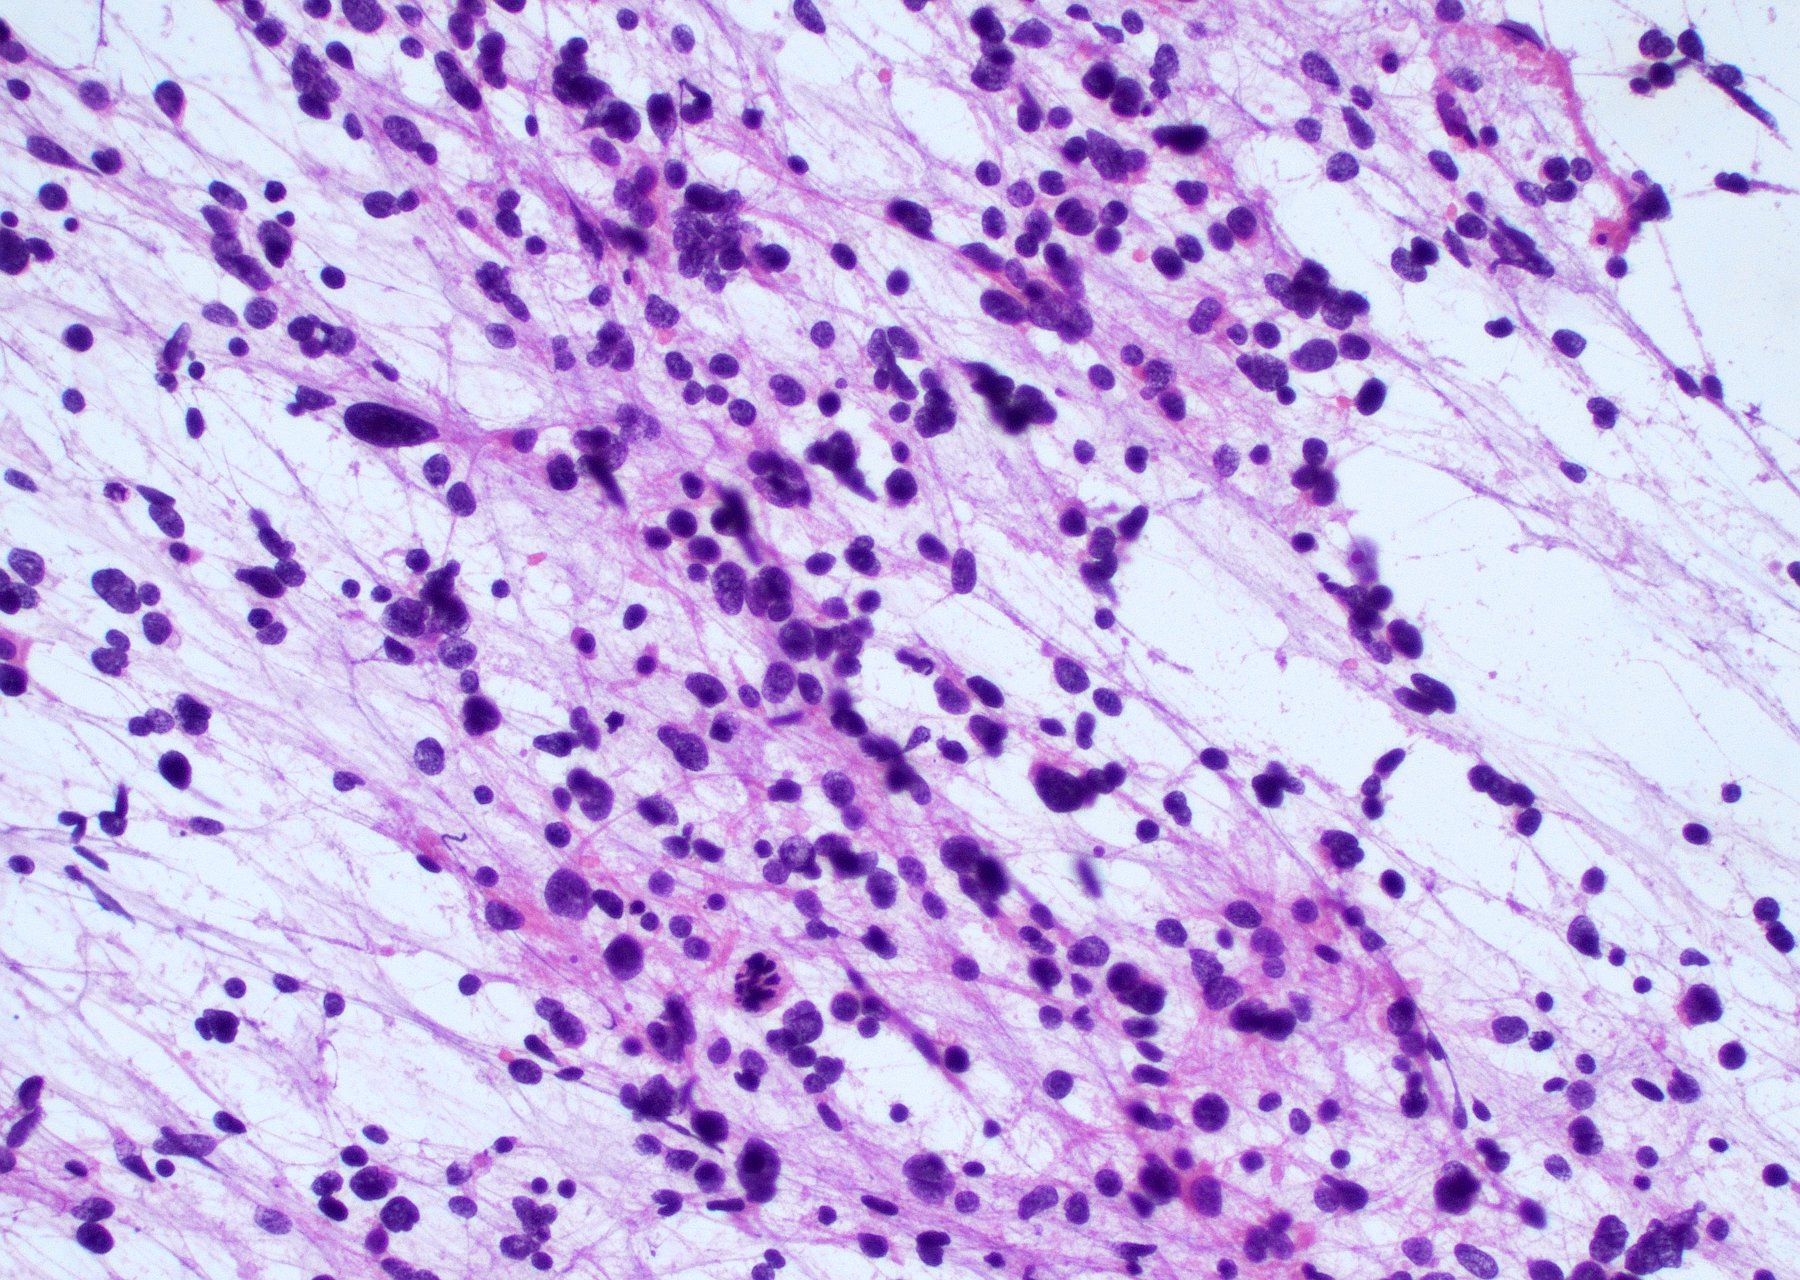

Intraoperative frozen / smear cytology images

Microscopic (histologic) description

Cytology description

- Intraoperative smears may show marked cellularity, with moderate to markedly pleomorphic astrocytic / gemistocytic cells with fine fibrillar glial processes (Diagn Cytopathol 1986;2:312)

- May show necrosis

- Mitotic figures can be observed